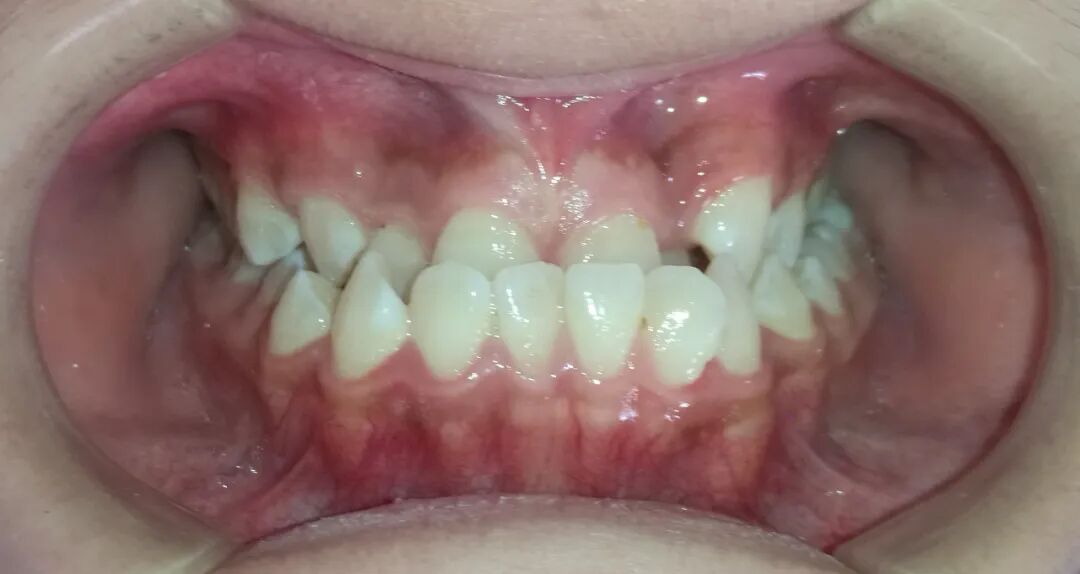

病例2

治疗前